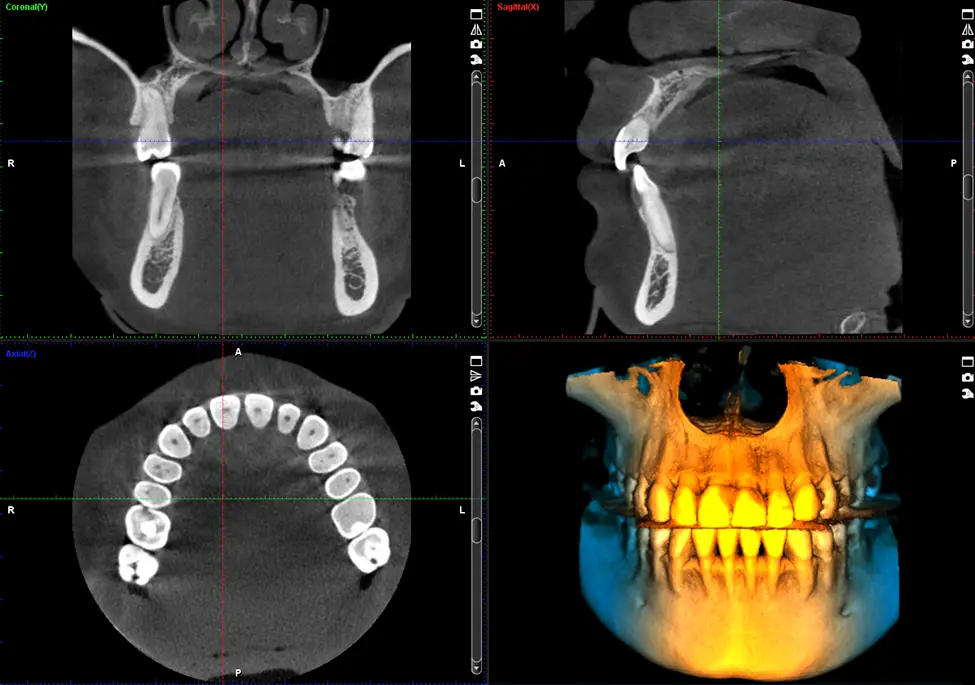

Computer tomografia dentară (CBCT)

Tomografia computerizată dentară (CBCT) oferă imagini tridimensionale detaliate ale dinților, osului maxilar și structurilor anatomice învecinate.

Această investigație este esențială pentru planificarea tratamentelor complexe precum implanturile dentare, chirurgia orală sau tratamentele ortodontice. În clinica Omnia Dental, tomografia dentară este realizată cu echipamente moderne, care permit obținerea unor imagini precise cu o doză redusă de radiații.